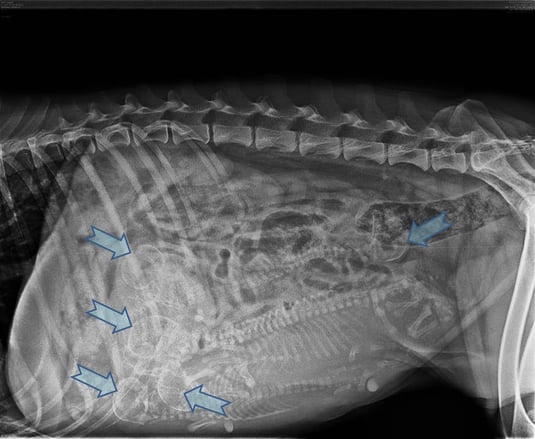

Am rechnerisch 58. Tag der Belegung erfolgte dann die Röntgendiagnostik, um so eine Mengenbestimmung vornehmen zu können. Fünf Köpfe und Wirbelsäulen waren zu erkennen.